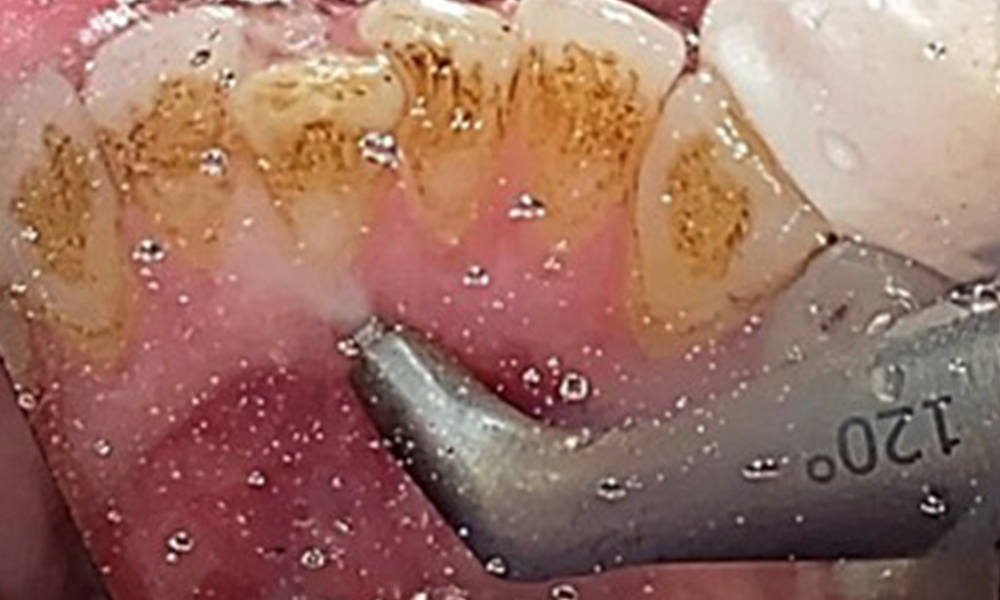

The objective would be to control disease risk by removing supragingival and subgingival biofilm. The instruments can be selected based on patient needs. First, calculus and any concretions must be removed using ultrasonic and/or manual instruments (Fig. 10).